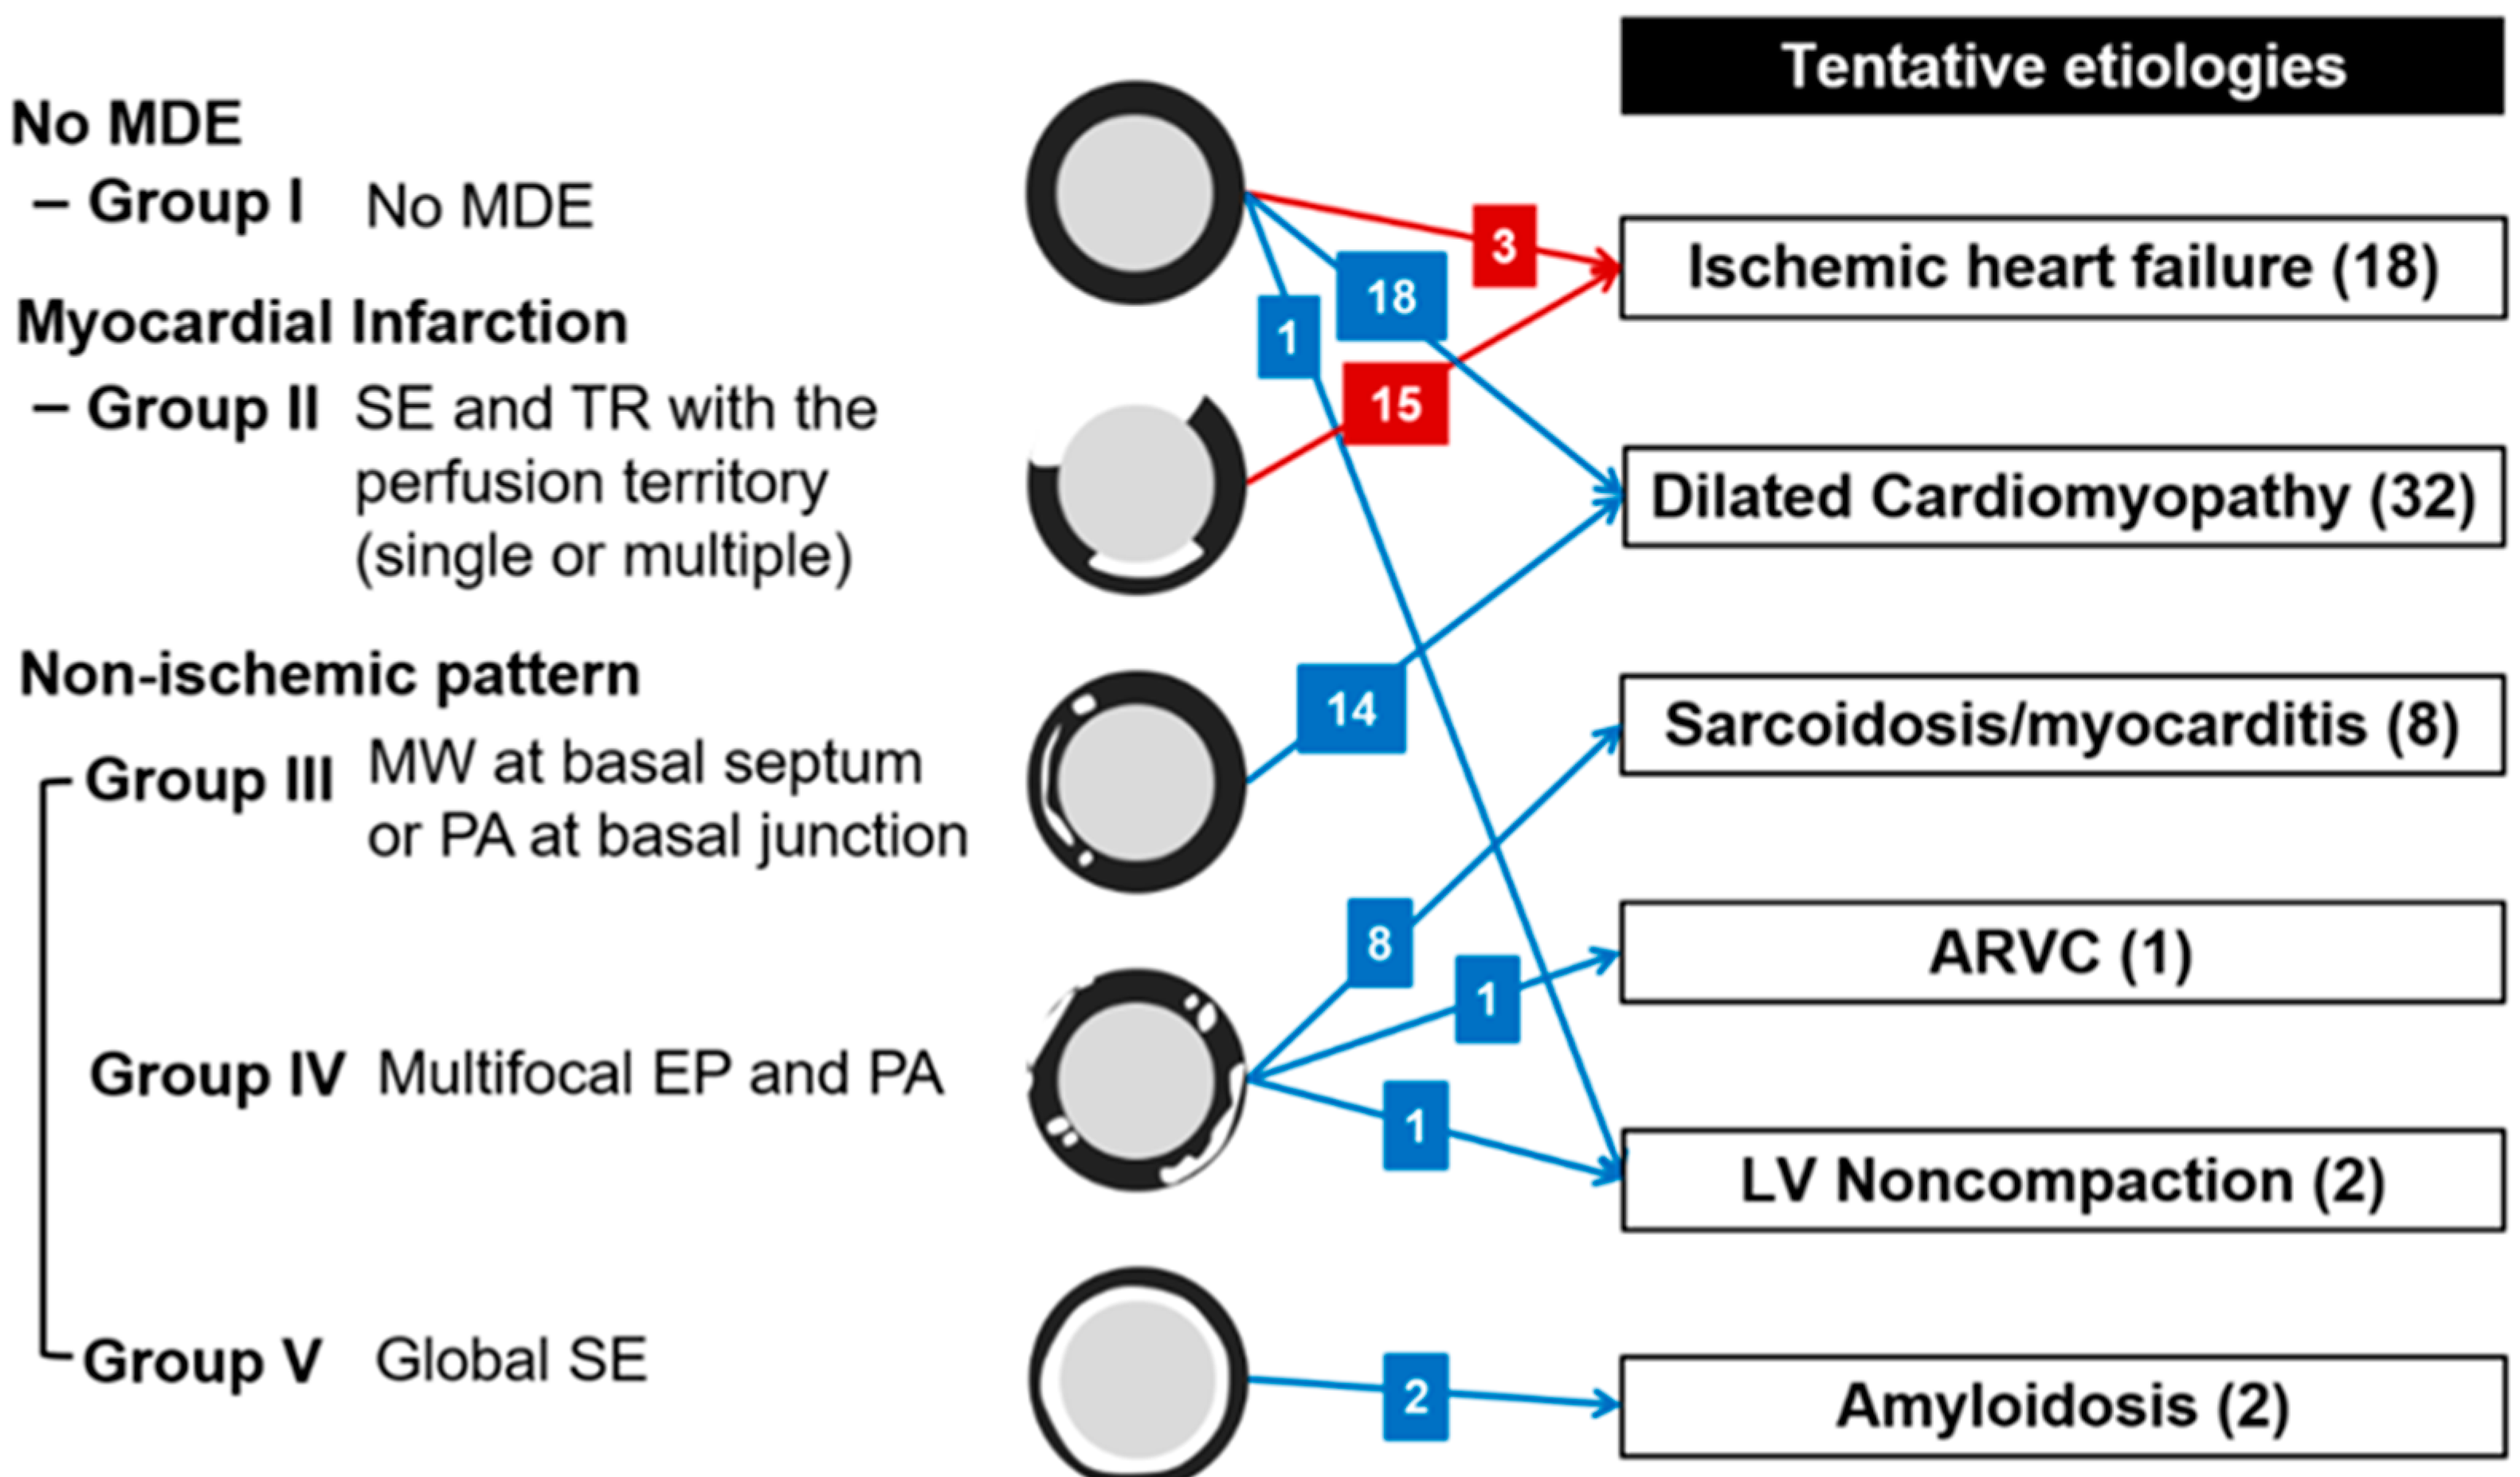

3.4. Tentative Etiologies of HF from Cardiac CT